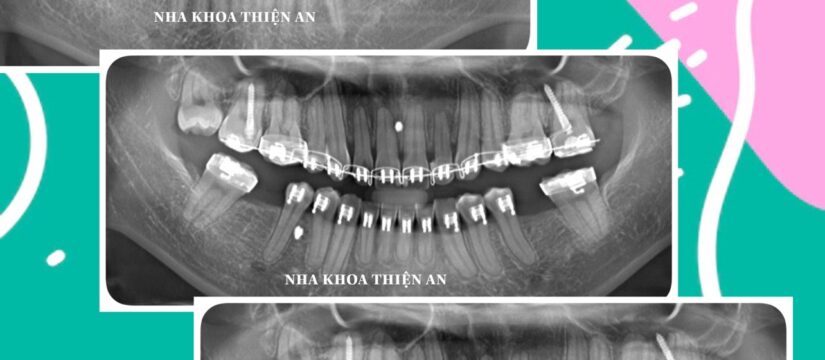

Chỉnh nha hỗ trợ điều trị nghiến răng, rối loạn khớp thái dương hàm và tạo khoảng để trồng lại 2 răng mất cho bạn T (25 tuổi) tại nha khoa Thiện An BMT – Đăk Lăk. Chỉnh nha kết hợp cùng implant

Phối hợp nhịp nhàng giữa bác sỹ chỉnh nha và bác sỹ implant để vừa điều trị bệnh lý, cải thiện thẩm mĩ, chức năng ăn nhai cho quý khách hàng thân yêu

Orthodontics supports the treatment of teeth grinding, temporomandibular joint disorders and creates space to replant 2 missing teeth for Ms. T (25 years old) at Thien An BMT Dental Clinic – Dak Lak

Smooth coordination between orthodontists and implant doctors to treat diseases, improve aesthetics, and chewing function for our dear customers